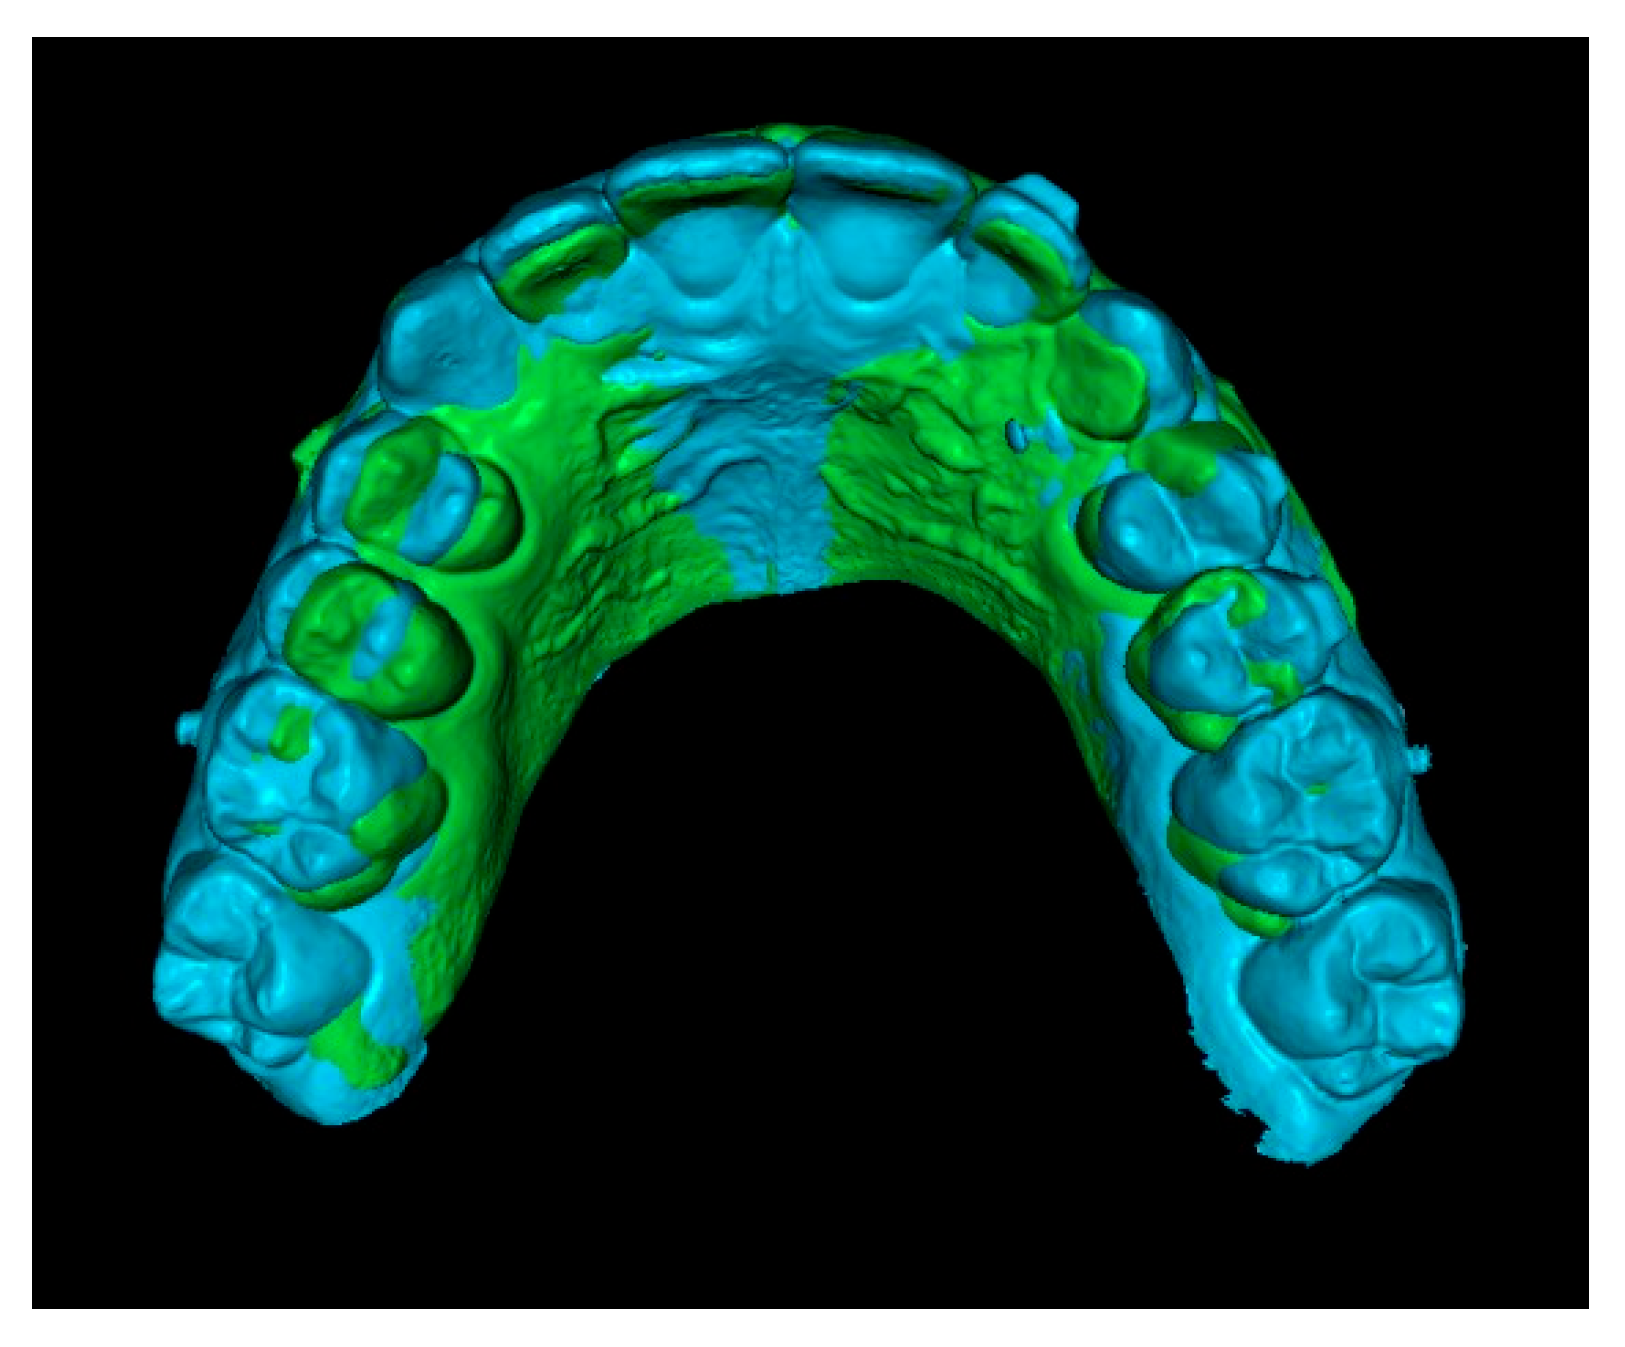

Second step: Superimposition of Initial CBCT and Initial STL Scans.

In this step, the segmented teeth from the initial CBCT scan were superimposed onto the initial STL file. This was achieved by marking corresponding points on several teeth throughout the dental arch, ensuring accurate alignment (Figure 4). Despite the morphological differences between the CBCT and STL models, particularly related to the canine region, as the permanent canine was still impacted and therefore visible only in the CBCT, corresponding anatomical landmarks were carefully selected on both models to enable accurate superimposition and comparison. The deciduous canine is only visible in the intraoral scanner data, as it was not segmented and included in this figure despite being present in the CBCT (Figure 4).

Figure 4.

Superimposition of segmented teeth from initial CBCT and initial STL.

Since orthodontic traction had not yet started, the position of the teeth remained unchanged between scans, allowing precise registration. As a result, the initial STL was effectively combined with the three-dimensional position of the IC derived from the CBCT (Figure 5).

Figure 5.

Initial STL with the IC from the CBCT scan.

Third step: Overlay of Initial STL with IC and Final STL.

The initial STL combined with the IC was superimposed onto the final STL by marking stable reference points on the palatal rugae (Figure 6). This process resulted in a final STL model that includes the initial position of the IC (Figure 7).

Figure 6.

Superimposition of initial and final STL models using palatal rugae.

Figure 7.

Final STL including the initial 3D position of the IC.